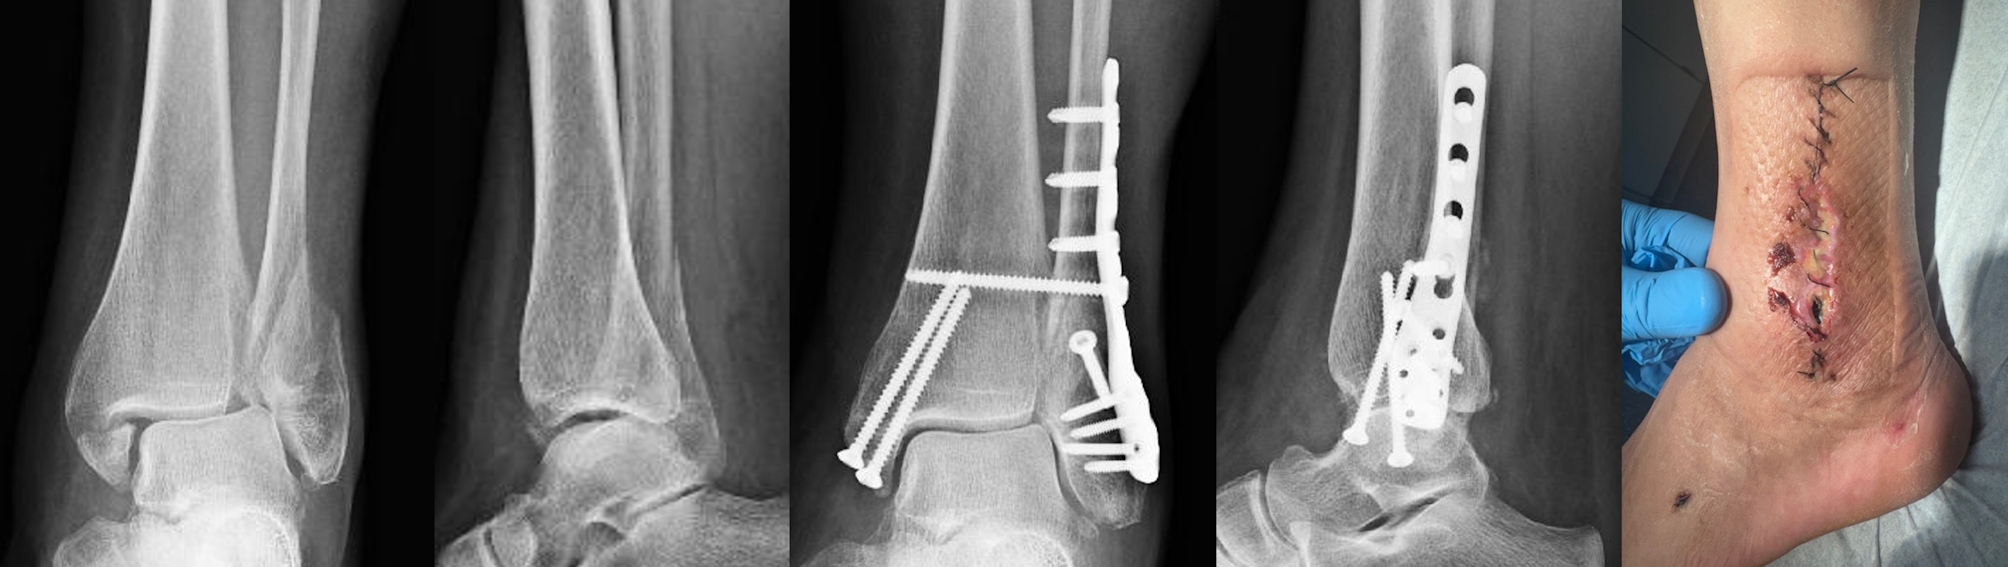

Background: The clinical benefit of locking plates in distal fibula fractures has not yet been proven. In addition, the risk of wound complications appears to be higher than with conventional tubular plates. We hypothesize that the benefits of locking plates in terms of biomechanical properties are outweighed by a higher risk of wound complications.

Methods: We conducted a retrospective review of fibula fractures treated by osteosynthesis with either a conventional one-third tubular plate or an anatomically shaped locking plate from January 1, 2015 to December 31, 2021. We recorded baseline data and relevant comorbidities and defined the need for revision surgery due to wound-related or mechanical complications as primary endpoints.

Results: A total of 595 out of 727 patients were eligible for our study. Of these 595 fractures, 526 were fixed with a one-third tubular plate, 69 with a locking plate. Revision surgery was required in 54 patients, in 51 cases due to wound complications. Three patients required revision surgery for mechanical reasons and all of them were younger than 40 years of age, have not been diagnosed with osteoporosis, but experienced complex fracture types. As the third tubular plate and locking plate groups differed in terms of age and comorbidities, we performed a 2:1 matching based on age and gender, leaving data from 138 patients receiving a third tubular plate. While the two groups were comparable in many aspects, the rate of wound complications was significantly higher in the locking plate group. Although the locking plate group had a higher percentage of diabetes mellitus, there was no correlation between this comorbidity and the higher revision rate in this group.

Conclusions: Our data do not support the general use of locking plates in the treatment of distal fibular fractures. The risk of mechanical complications in osteoporotic ankle fractures seems to be overrated, as there were no mechanical revisions in the osteoporotic subgroup. The rate of wound-related revision surgery was significantly higher after the use of locking plates. This might be attributed to the greater thickness of locking plates.